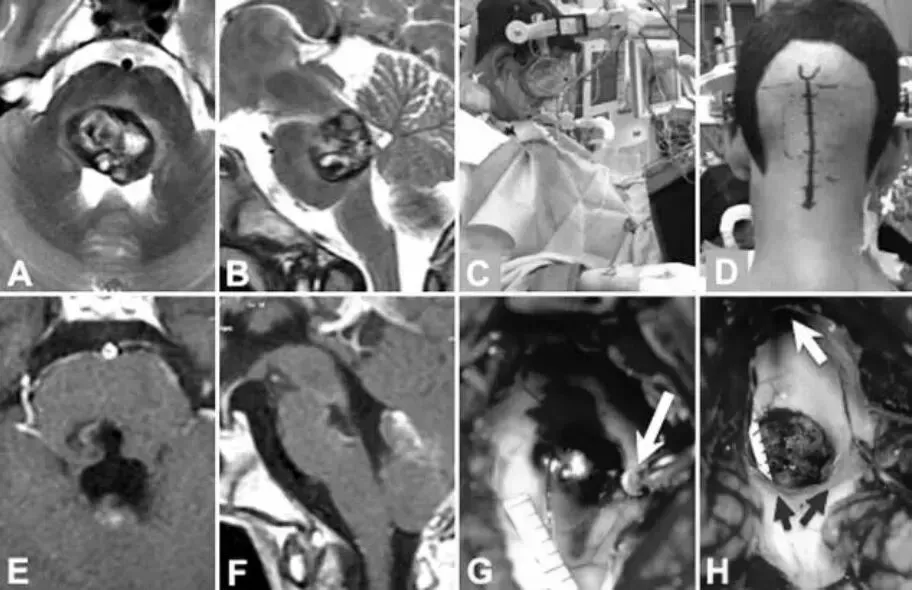

45岁的女性患者因脑桥大量急性出血被紧急送入医院。到院时,她已出现意识障碍,四肢完全瘫痪,无法自主翻身。临床症状表现为左侧偏瘫与偏侧感觉减退,右侧面瘫、第六神经麻痹,同时伴有严重的吞咽困难——这些症状组合在一起,清晰地指向了极为危重的病情状态。

影像学检查所见印证了这一判断:患者脑桥中央区域存在一个巨大的海绵状血管瘤,病变已向下压迫至第四脑室底部,周围的神经结构受到极度推挤,变得菲薄。在这种情况下,保守治疗几乎等同于被动等待病情进一步恶化,手术是当时唯一能够逆转局势的选择。

手术在公园长椅位体位下实施,巴教授选择左侧远外侧经髁入路,精确绕开了关键神经核团,经由桥髓沟进入脑桥,将病变完整切除。术中观察到面神经在离开脑干水平处存在轻微出血点,在手术过程中被仔细识别并予以保护。

术后患者恢复过程平稳,无任何新发并发症出现。一年后的随访结果显示,这位曾一度命悬一线的患者已完全康复,日常生活自理,仅残留右侧面部轻微面瘫。从完全卧床到重新自立生活,这是精湛手术技术所创造的结果。

病例二:16岁男性——精准避开面神经,与面瘫擦肩而过

16岁的男性患者因左侧感觉运动综合征和核间性眼肌麻痹就诊。脑干内的海绵状血管瘤体积已相当可观,且病变位置与面神经紧密毗邻。所幸在就诊时,患者尚未发生面瘫,为手术保留了一个关键的功能保护窗口。

影像学评估显示,这是一例典型的B型脑桥海绵状血管瘤,病变向第四脑室底部突出生长。巴教授采用背中线入路,在半坐位下实施枕下开颅手术。整个术中过程中,神经电生理监测持续应用——外科医生借助刺激探针对双侧面神经的走行范围进行实时精准定位,确保手术操作路径自始至终与这些关键结构保持安全距离。

手术最终实现了病灶的完整切除,术后影像学检查可见毫米级的清晰残腔,面神经功能完整保留,未受任何损伤。这位年轻患者术后恢复迅速,顺利回归正常的学习和生活。